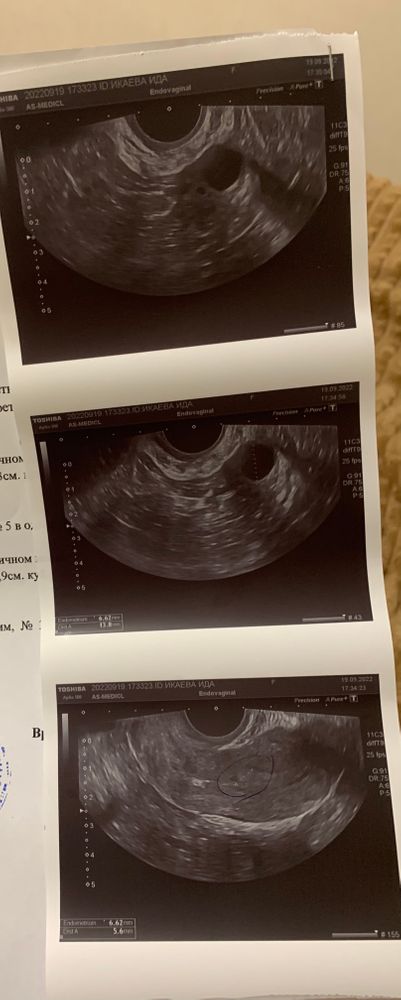

Прошлый цикл был 42 дня , обычно бывает 32-33. Сказали у меня киста желтого тела поэтому задержка . Месячные были всего 3 дня .обычно бывает 5-6. Подумала вряд ли уйдёт киста если не обильные месячные . Пошла на узи на 5дц врач узи сказала что киста рассосалась. Ты говорит пила какие то препараты я говорю нет. Когда уже уехала увидела на узи что там жт 17мм. Значит не ушла киста да ? Сегодня повторно была у нее . На 19дц раньше всегда на 19-21 день была овуляция. Я даже как будто почувствовала его .

Если я правильно поняла то на 5 дц у вас еще не видно ни доминантных фолликулов,ни хорошего эндометрия нет(м-эхо)это эндометрий.

на 19дц у вас уже судя по ЖТ была овуляция(странно что про жидкость в позадиматочном пространстве не указано.она после овуляции всегда бывает) но на 19 дц у вас все еще тонковат эндометрий(для благоприятного исхода хотябы от 7 мм врачи говорят)

по полип ерунда какая то,знаю по себе что во вторую фазу цикла они не смотрятся на узи,тк нарастает эндометрий, и полипы нужно смотреть на 5 дц.(по узи у вас его нет на 5 дц)

узист сказал что вероятно будет задержка месячных потому что тонковат эндометрий и отторгаться по сути нечему,по этому этот цикл мб подольше, хотя овуляция была и вторая фаза должна длиться ровно 14 дней)